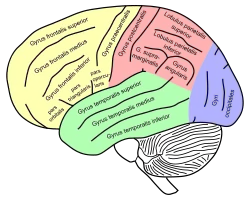

Animation. Inferior parietal lobule is shown in red. Lateral view of a human brain, main gyri labeled.

Lateral view of a human brain, main gyri labeled. Cerebrum. Lateral view. Deep dissection.